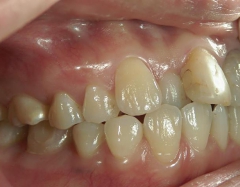

矯正歯科 治療後矯正歯科 プチワイヤー矯正 治療後矯正歯科(プチワイヤー矯正)治療後

矯正歯科 治療後  スペース確保の為、 2番抜歯

no.37_7548_治療後_右.JPGno.37_7548_治療後_正面.JPGno.37_7548_治療後_左.JPG